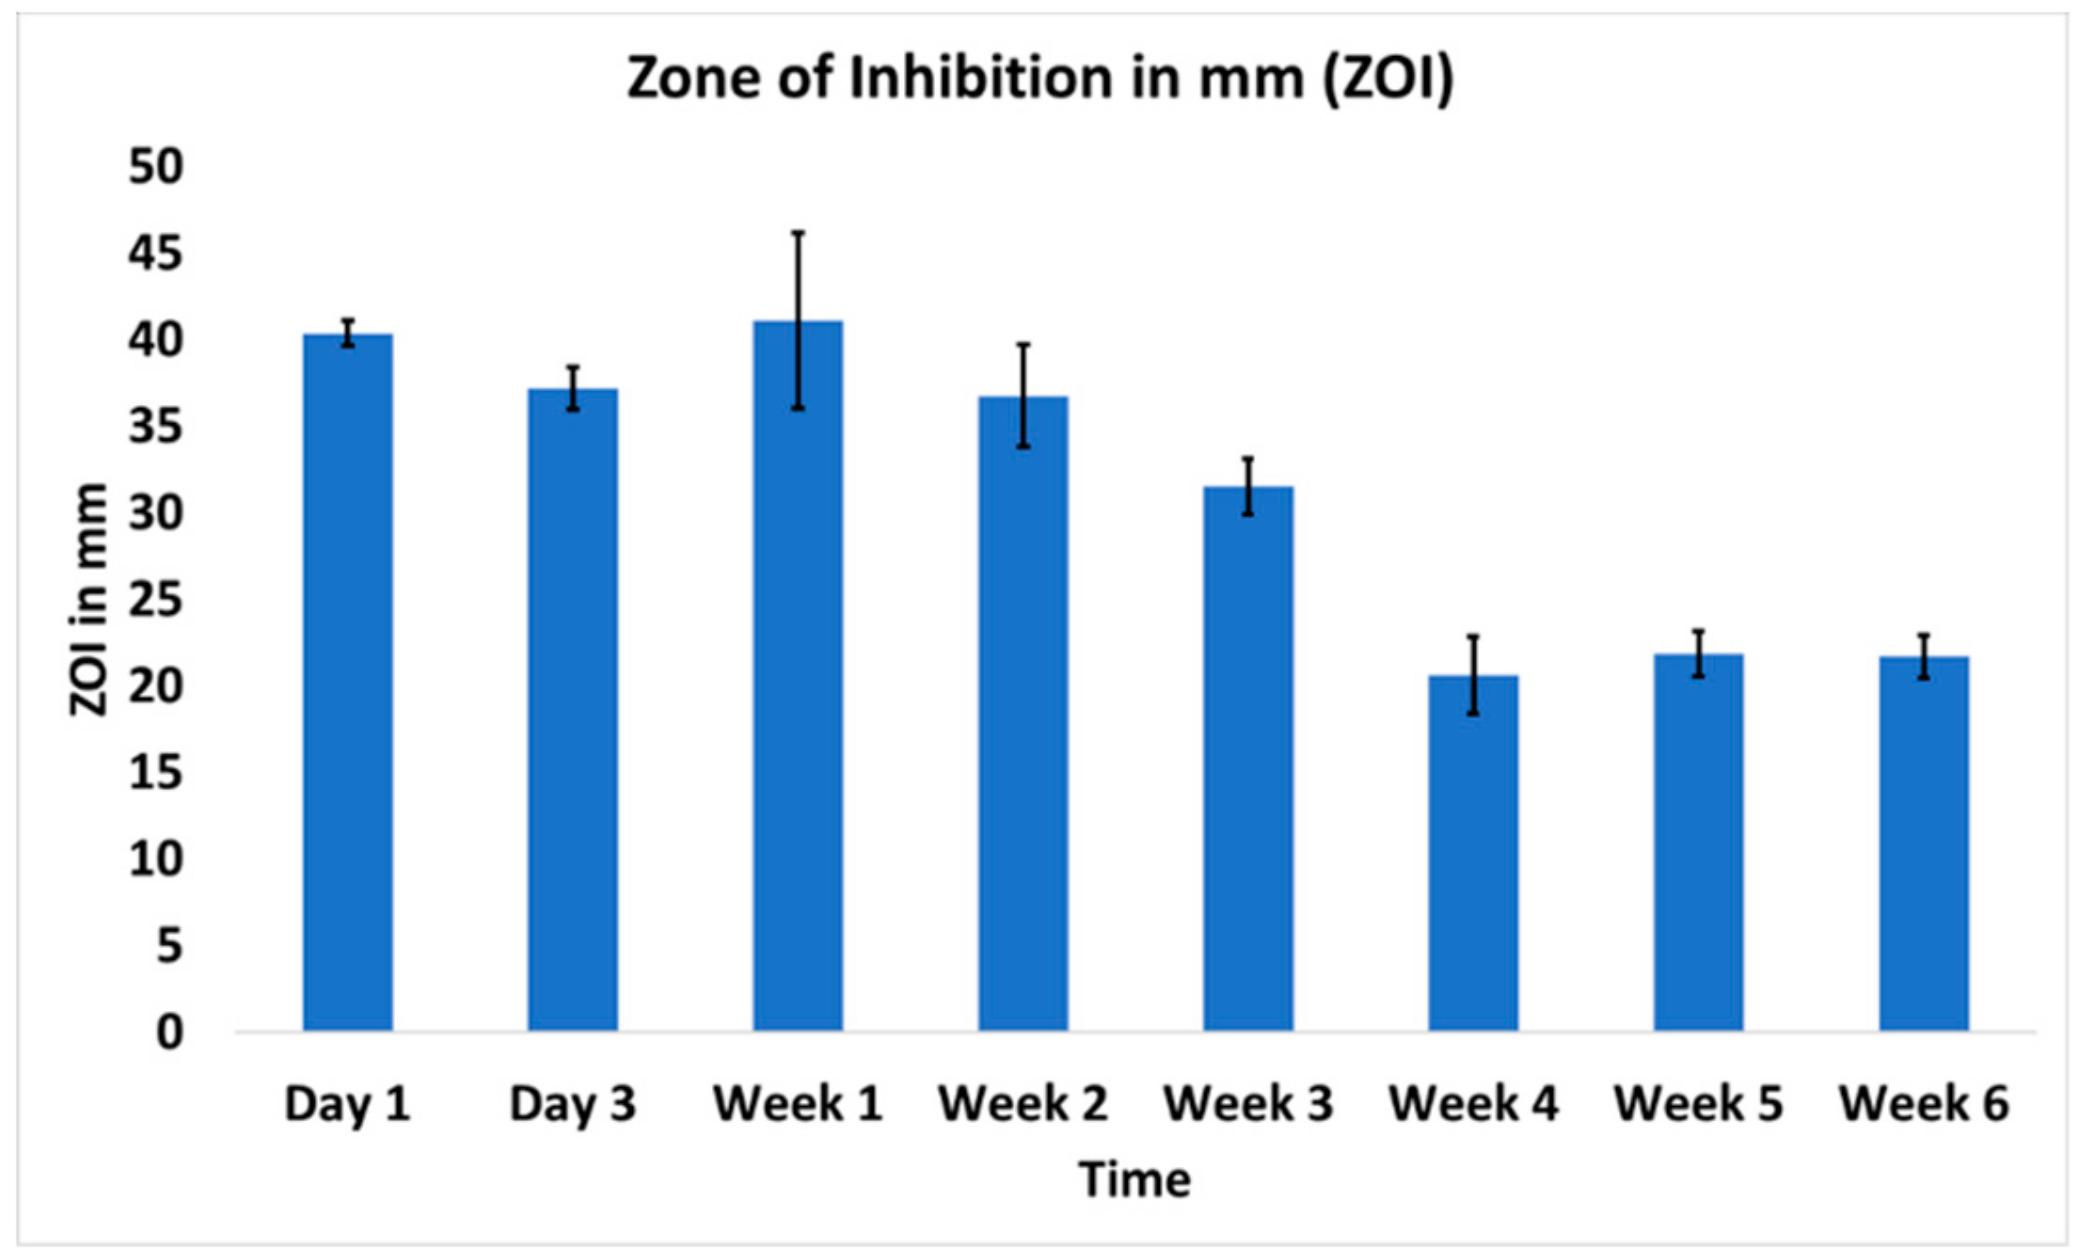

2.3.3. In Vitro Antibacterial Activity

3.3. In Vitro Antibiofilm Assay

3.4. In Vitro Cytocompatibility

4. Discussion